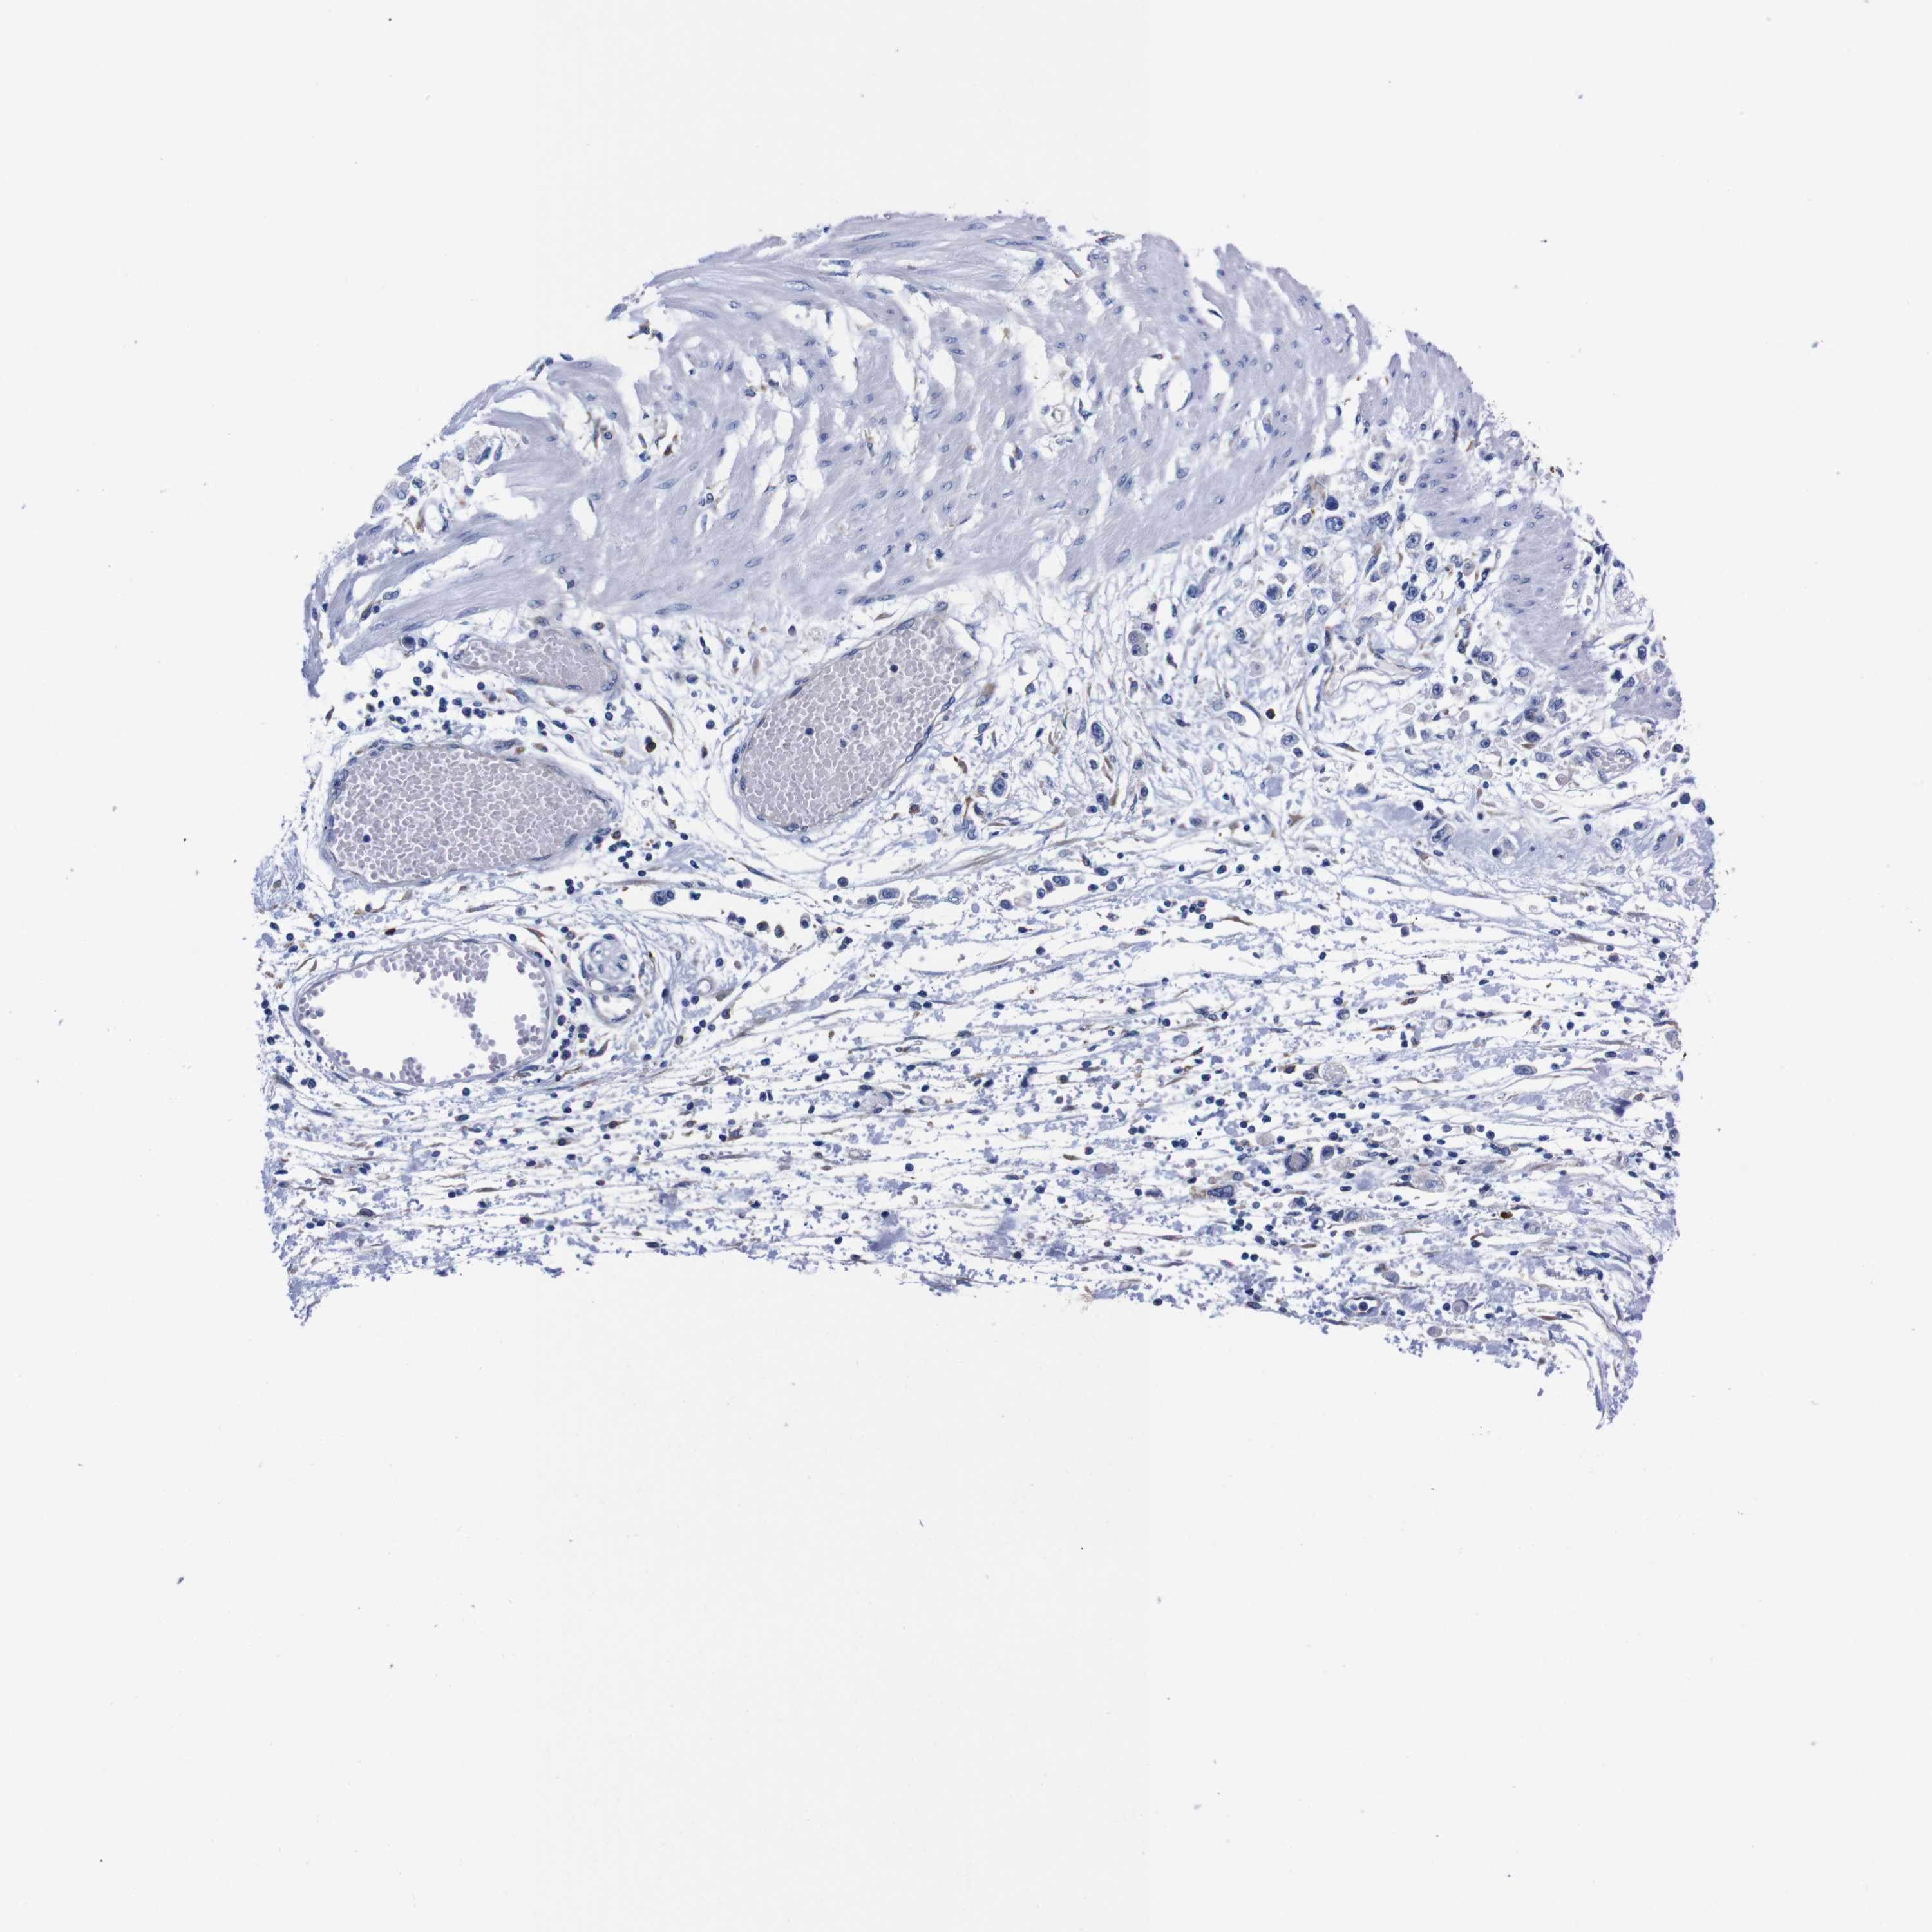

STOMACH CANCER - Protein expressioni

A mouse-over function shows sample information and annotation data. Click on an image to view it in a full screen mode. Samples can be filtered based on level of antibody staining by selecting one or several of the following categories: high, medium, low and not detected. The assay and annotation is described here.

Antibody stainingi

Antibody staining in the annotated cell types in the current human tissue is reported as not detected, low, medium, or high, based on conventional immunohistochemistry profiling in selected tissues. This score is based on the combination of the staining intensity and fraction of stained cells.

Each image is clickable and will lead to virtual microscopy that enables deeper exploration of all samples and also displays staining intensity scores, fraction scores and subcellular localization as well as patient and tissue information for each sample.

Antibody HPA013994

Antibody HPA013995

Staining

High

Medium

Low

Not detected

Intensity

Strong

Moderate

Weak

Negative

Quantity

>75%

75%-25%

<25%

None

Location

Nuclear

Cytoplasmic/membranous

Cytoplasmic/membranous,nuclear

Adenocarcinoma, NOS

Adenocarcinoma, High grade